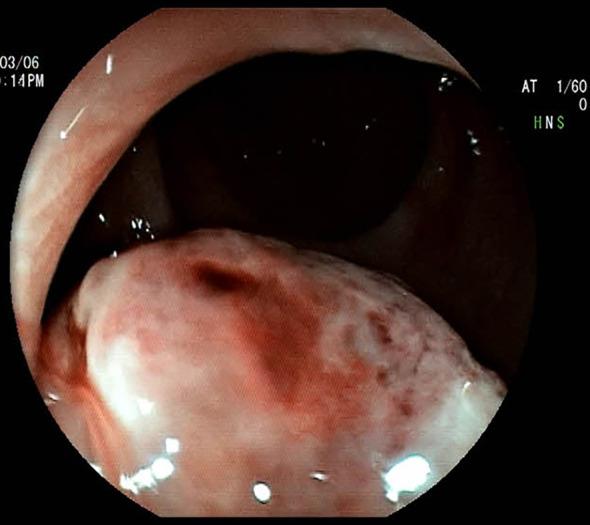

This report details the case of a 51-year-old woman presenting with persistent bright red blood in her stool. Digital rectal examination revealed a firm, spherical mass approximately 4 cm from the anal verge. Colonoscopy identified a pedunculated polypoid lesion (2.5 cm in diameter) near the anorectal junction. Based on clinical symptoms, physical findings, and endoscopic features, a high suspicion of rectal cancer was initially raised. However, subsequent histopathological evaluation of biopsy specimens revealed immunohistochemical positivity for MelanA, S100, and Ki-67 (30%), suggesting a probable diagnosis of malignant melanoma. After completing preoperative contrast-enhanced abdominal CT and pelvic MRI examinations and excluding surgical contraindications, the patient underwent laparoscopic-assisted abdominoperineal resection (Miles procedure) and postoperative adjuvant therapy with toripalimab. Moreover, no signs of recurrence were found during follow-up over 3 months postoperatively.

本报告详细介绍了一名51岁女性患者,其粪便中持续出现鲜红色血液。直肠指检发现距肛缘约4厘米处有一个质地坚硬的球形肿块。结肠镜检查发现肛管直肠交界处附近有一个带蒂的息肉样病变(直径约2.5厘米)。根据临床症状、体格检查结果和内镜特征,最初高度怀疑为直肠癌。然而,随后活检标本的组织病理学评估显示MelanA、S100和Ki-67(约30%)免疫组化呈阳性,提示可能诊断为恶性黑色素瘤。在完成术前腹部增强CT和盆腔MRI检查并排除手术禁忌证后,患者接受了腹腔镜辅助腹会阴联合切除术(Miles手术)及术后托瑞帕利单抗辅助治疗。此外,术后3个月以上的随访期间未发现复发迹象。